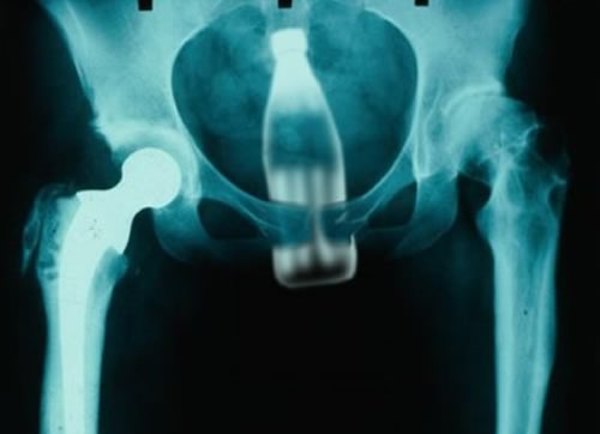

Nevjerovatan je spisak predmeta koje su našli u tijelima pacijenata. To su vibratori, banane, poklopci od sprejova, manje boce... U većini slučajeva, osobe s ovim problemom odlaze kod hirurga tek onda kada nemaju drugog izlaza. Takve intervencije obično se okončaju bez operacije.

Statistike koje vode pojedini medicinski časopisi o ovim intervencijama u svijetu i zemljama okruženja, kako prenose mediji, pokazuju da ljekari iz anusa svojih pacijenata vade: boce, šolje, drške od metle, kravlje rogove, ručne svjetiljke, teniske loptice, banane, krastavce...